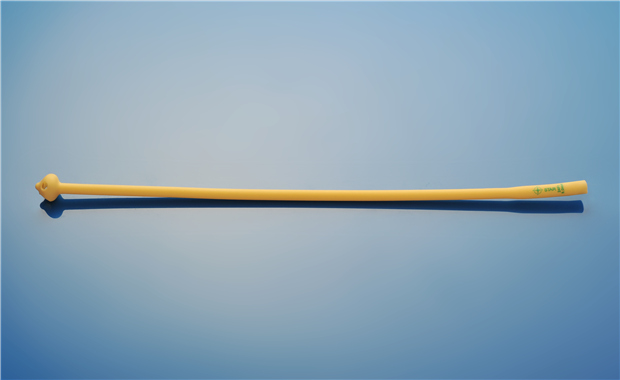

【產品名稱】一次性使用單腔導尿管(PVC成人型) 【型號規格】12Fr、14Fr���、16Fr���、186Fr、20Fr���。 【性能���、主要結構】 由醫用PVC粒料為主要原材料制成,由排泄錐形接口��、管身��、排尿孔組成�����。